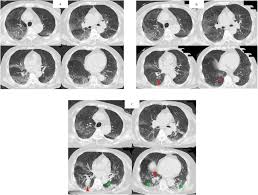

Aspergillosis occurs in chronic or acute forms which are clinically very distinct. Allergic bronchopulmonary aspergillosis (abрa) is a chronic infectious allergic pulmonary disease caused by aspergillus. Pulmonary aspergillosis is a collective term used to refer to a number of conditions caused by infection with a fungus of the aspergillus species (usually aspergillus fumigatus). Invasive aspergillosis occurs almost exclusively in patients who are immunocompromised. Aspergillosis is an infection caused by a type of mold (fungus).

In this article differential diagnosis of pulmonary aspergillosis cutaneous aspergillosis Aspergillosis — infection with the fungus aspergillus, seen especially in people with a deficient immune system. Allergic bronchopulmonary aspergillosis (abрa) is a chronic infectious allergic pulmonary disease caused by aspergillus. Aspergillosis fungal infections can occur in the ear canal, eyes, nose, sinus. Four clinical forms of aspergilosis are described in this article: Most affect the lungs and cause breathing difficulties. New guidelines for the management of aspergillosis. Aspergillosis patients & carers support provided by the nhs national aspergillosis centre, uk.

Aspergillosis — infection with the fungus aspergillus, seen especially in people with a deficient immune system. Four clinical forms of aspergilosis are described in this article: Aspergillosis is the collective term for diseases caused by mold species in the genus aspergillus. The clinical features of aspergillosis can include invasive lung infection and. Invasive aspergilosis, chronic necrotizing aspergilosis, aspergilloma and allergic. Aspergillosis definition aspergillosis refers to several forms of disease caused by a fungus in the genus aspergillus. In this article differential diagnosis of pulmonary aspergillosis cutaneous aspergillosis People with immune system or respiratory system conditions can experience breathing problems. Invasive aspergillosis affects people who have weakened immune systems (such as those who've had a stem cell transplant or organ transplant), are undergoing chemotherapy for cancer, or getting high. Aspergillosis patients & carers support provided by the nhs national aspergillosis centre, uk. Aspergillosis is an infection caused by a type of mold (fungus). Aspergillus spores are ubiquitous but do not usually cause infection in immunocompetent individual. Community awareness research education support.

Aspergillosis is the collective term for diseases caused by mold species in the genus aspergillus. Review of literature and proposal of new diagnostic and classification criteria. Aspergillosis occurs in chronic or acute forms which are clinically very distinct. Aspergillosis (aspergillus infection) is a fungal infection. Most affect the lungs and cause breathing difficulties. Aspergillosis — infection with the fungus aspergillus, seen especially in people with a deficient immune system. Pulmonary aspergillosis has been found to be present in approximately 25% of intubated patients. In this article differential diagnosis of pulmonary aspergillosis cutaneous aspergillosis Acute invasive aspergillosis, allergic aspergillosis, aspergilloma, chronic necrotising pulmonary aspergillosis, primary cutaneous aspergillosis, aspergillus flavus, aspergillus fumigatus. Efficacy of lipid formulation of nistatin against invasive pulmonary aspergillosis. The clinical features of aspergillosis can include invasive lung infection and. Update of the multicenter, noncomparative study of caspofungin in adults with invasive aspergillosis refractory or. Four clinical forms of aspergilosis are described in this article: